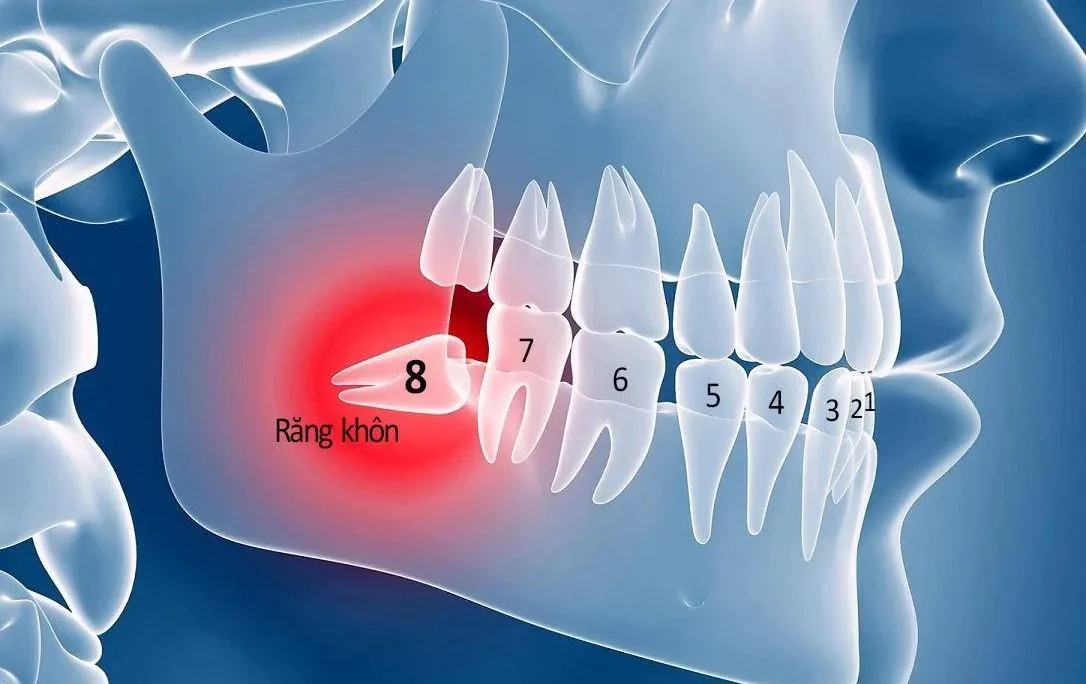

Răng số 6, hay còn gọi là răng cấm, răng hàm lớn, là răng mọc vĩnh viễn đầu tiên và đóng vai trò vô cùng quan trọng trong hệ thống răng miệng. Chiếc răng này đảm nhận chức năng nghiền nát thức ăn, hỗ trợ tiêu hóa và duy trì cấu trúc hàm mặt. Vì răng số 6 chỉ mọc một lần, khi mất răng này sẽ gây ra nhiều vấn đề nghiêm trọng như:

- Xô lệch răng lân cận: Các răng xung quanh có xu hướng nghiêng về phía khoảng trống, gây mất thẩm mỹ và khó vệ sinh.

- Tiêu xương hàm: Do không có chân răng kích thích, xương hàm tại vị trí răng mất sẽ dần bị tiêu đi.

- Ảnh hưởng đến khớp cắn: Gây mất cân bằng lực nhai, dẫn đến các vấn đề về khớp thái dương hàm.

- Hóp má: Mất răng số 6 lâu ngày có thể gây hóp má, làm thay đổi cấu trúc khuôn mặt.